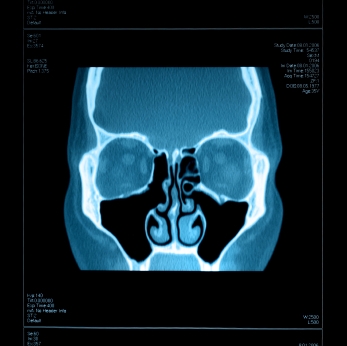

Компьютерная томография головы

Описание услуги - Компьютерная томография головы

Специальный рентген, который позволяет врачу увидеть аномалии мозга. Этот тест часто используется для выявления травм головного мозга, кровоизлияние в мозг, инсульт, абсцессы мозга и перелом черепа. Тест чаще всего делается без внутривенного красителя (контраст), но также может быть сделано с контрастом, чтобы лучше визуализировать сосуды, инфекции и рак.